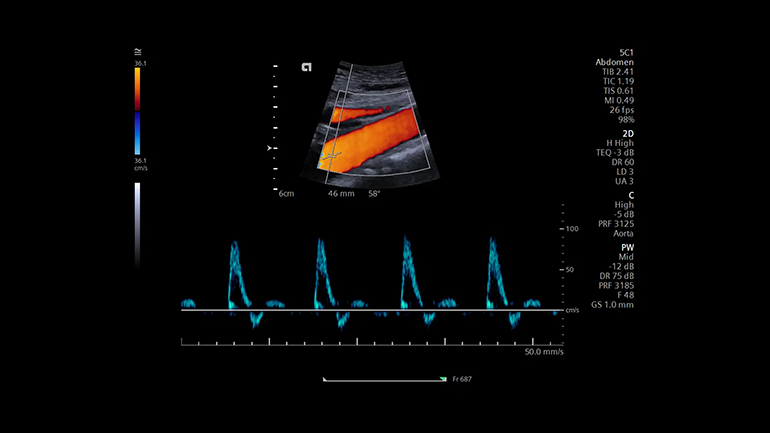

Технология UltraArt — одновременный вывод четырех изображений в режиме реального времени на сенсорный экран с предустановленными различными настойками визуализации. Инновационная технология обработки эхо-сигнала UltraArt Universal Image Processing компании Siemens Healthineers позволяет выводить изображения на экран с предустановленными программными настойками. Выбор параметров визуализации можно определить одним нажатием кнопки на четырехкадровом дисплее в режиме реального времени. Эта технология позволяет улучшить контрастное разрешение различных анатомических структур, повысить качество и уровень согласованности исследований среди разных пользователей благодаря исключению возможности выбора неправильных сочетаний отдельных параметров сканирования. Оптимизация ультразвукового исследования с помощью технологии Auto TEQ. Технология автоматической оптимизации AutoTEQ подстраивает соответствующие параметры визуализации, позволяя свести к минимуму действия врача-диагноста по настройке сканера. В B-режиме и в импульсном допплеровском режиме можно настроить одновременно несколько параметров сканирования — например, общее усиление сигнала, шкалу скорости и фильтр помех от движения стенок сосудов при пульсовой волне.

Оптимизация ультразвукового исследования с помощью технологии Auto TEQ. Технология автоматической оптимизации AutoTEQ подстраивает соответствующие параметры визуализации, позволяя свести к минимуму действия врача-диагноста по настройке сканера. В B-режиме и в импульсном допплеровском режиме можно настроить одновременно несколько параметров сканирования — например, общее усиление сигнала, шкалу скорости и фильтр помех от движения стенок сосудов при пульсовой волне.Дополнительные приложения